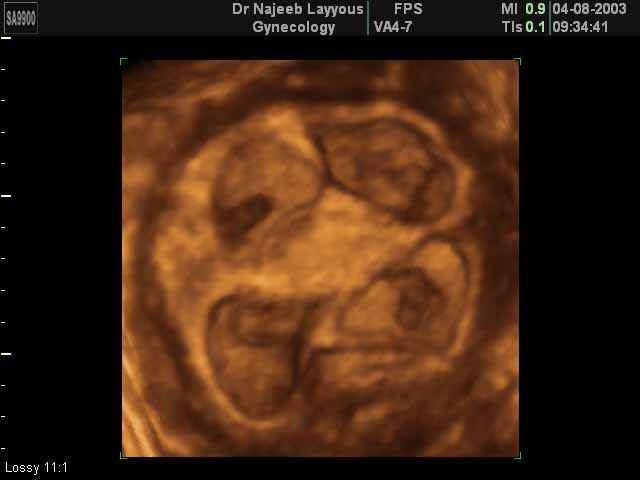

صور لتوائم بجهاز الالتراساوند ثلاثي الأبعاد | الدكتور نجيب ليوس

صور لتوائم بجهاز الموجات فوق صوتية ثلاثي الأبعاد